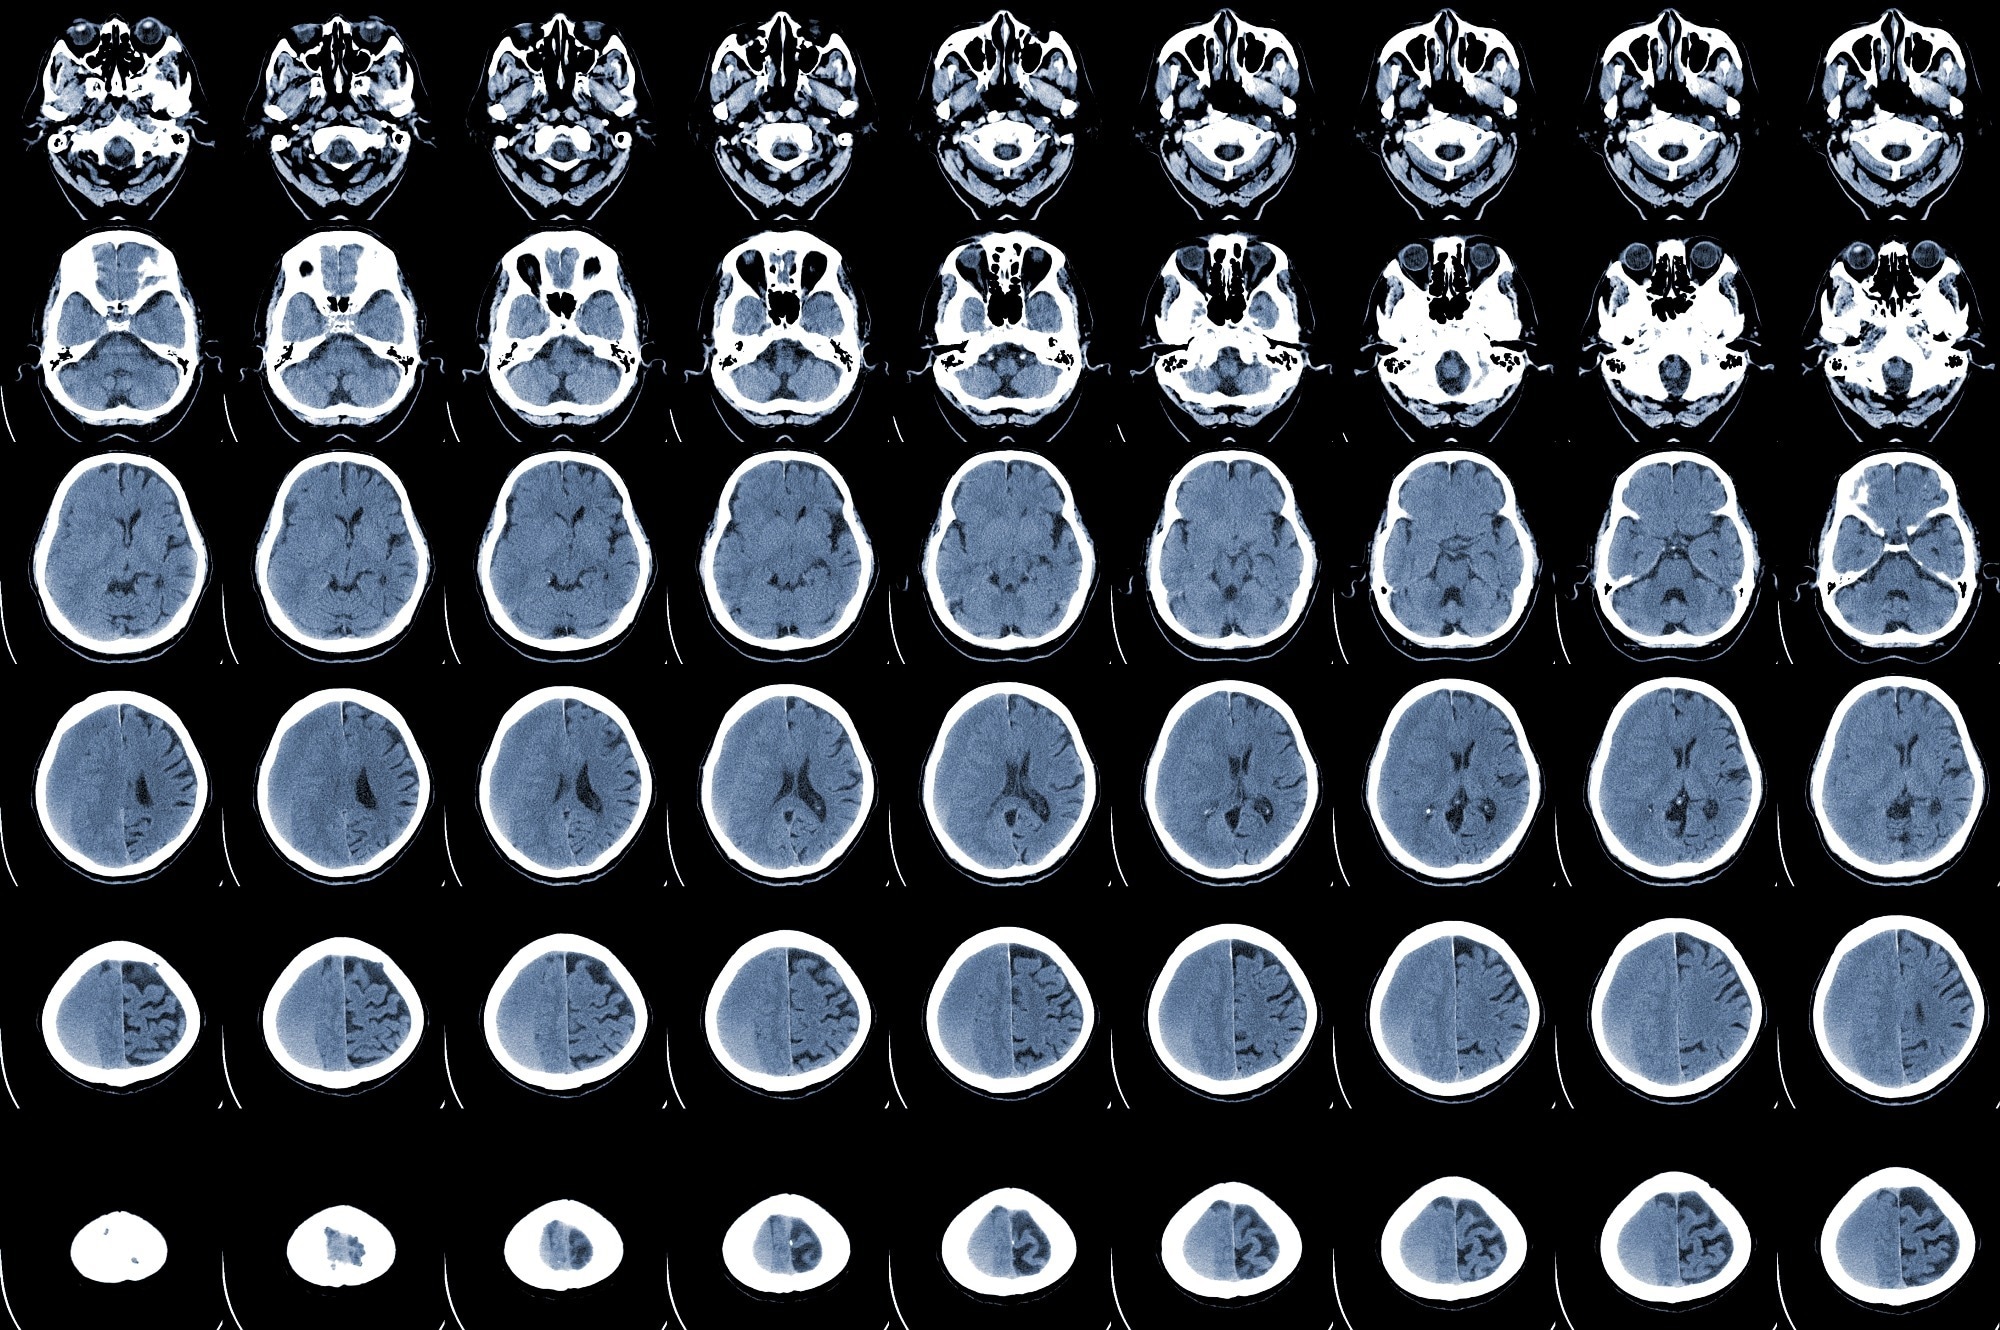

Study: The impact of SARS-CoV-2 infection on the outcome of acute ischemic stroke—A retrospective cohort study. Image Credit: April stock / ShutterstockStudy: The impact of SARS-CoV-2 infection on the outcome of acute ischemic stroke—A retrospective cohort study. Image Credit: April stock / Shutterstock

All AIS patients considered in this study exhibited acute neurologic signs of stroke and ischemia, confirmed using Magnetic Resonance Imaging (MRI) and Computed Tomography (CT) of the head. For this study, the authors collected relevant demographic data, medical history, stroke characteristics, length of hospitalization, in-hospital mortality, the number of patients transferred to an intensive care unit (ICU) facility, and laboratory test reports.